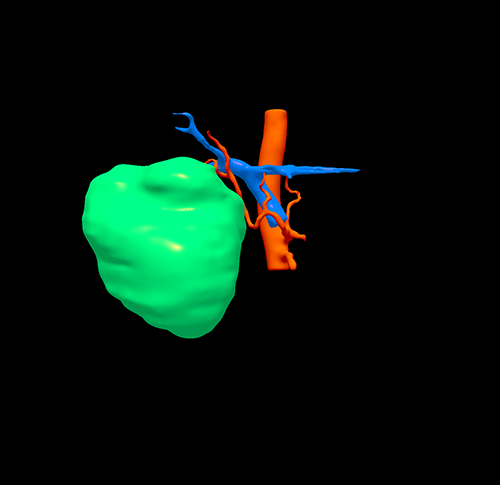

右肝巨大肝癌---右半肝切除